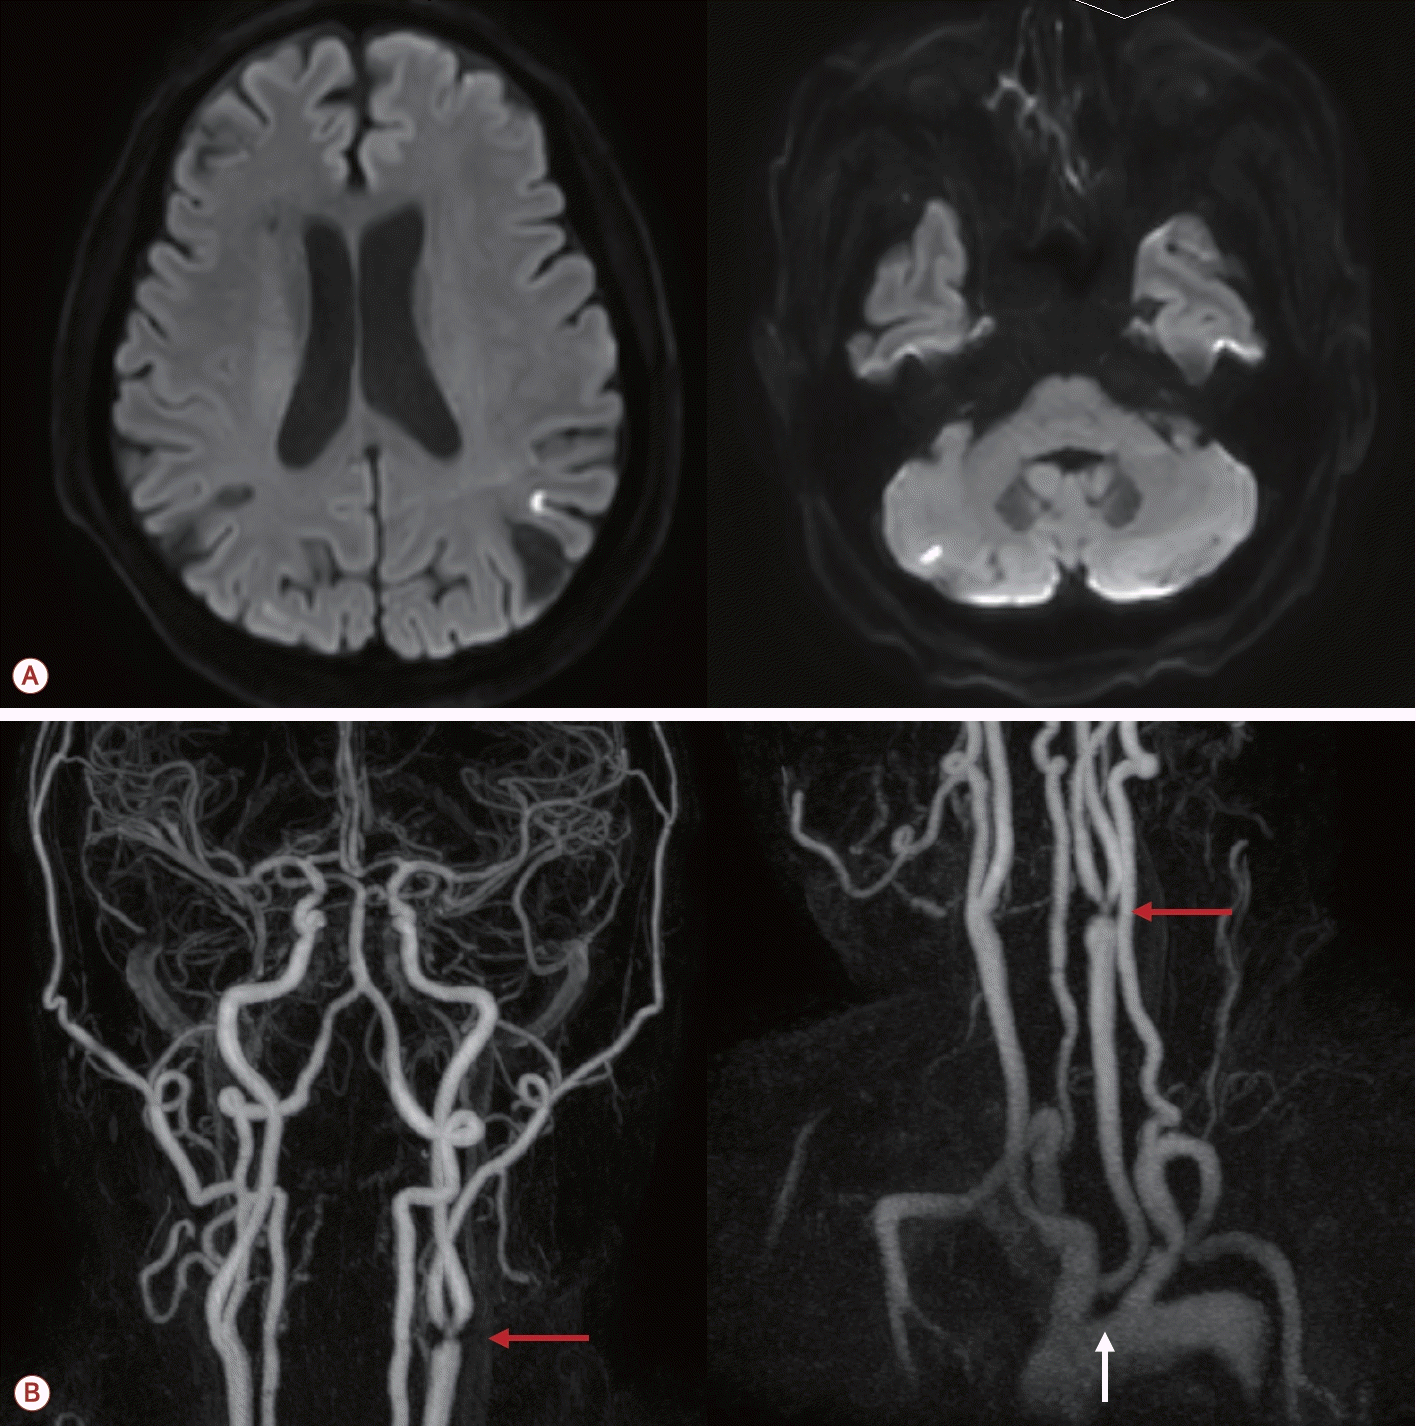

73세 남자가 최근 3개월간 반복적인 허혈뇌졸중으로 내원하였다. 환자는 고혈압, 당뇨, 안정협심증의 기저 질환을 가지고 있었다. 초기 뇌자기공명영상(magnetic resonance [MR] imaging)에서 좌측 대뇌반구와 우측 소뇌에 다발성 허혈 병변이 관찰되었으며(Fig. 1-A) 혈관 검사에서는 좌측 내경동맥근위부(internal carotid artery, ICA)에 76.7%의 협착(NASCET 기준)이 확인되었고 동시에 보바인형 대동맥궁(bovine arch, 공통 기시형 변이)이 관찰되었다(Fig. 1-B). 이에 따라 증상성 중증도 이상의 ICA 협착으로 판단하여 좌측 CEA와 이중 항혈소판 요법이 시행되었다. 그러나 시술 2개월 후에 우측 후 대뇌동맥(posterior cerebral artery, PCA)과 우측 중대뇌동맥(middle cerebral artery, MCA) 영역에 재발성 뇌경색이 발생하였고(Fig. 2-A) 한 달 후에는 좌측 MCA와 PCA 영역에 새로운 뇌경색이 재발하였다(Fig. 2-B). 기존에 진행되었던 두개경유도플러 검사에서 심방중격 결손이나 미세색전 신호를 시사하는 소견은 확인되지 않았고 흉부경유심초음파에서 좌심실 박출률은 정상 범위었으며 3일의 홀터 모니터링에서도 심방세동은 관찰되지 않아 심장성 색전은 배제하였다. 반복되는 색전성 병변의 원인을 찾기 위하여 식도유심초음파(transesophageal echocardiography, TEE)가 진행되었으며 대동맥궁 대만부(greater curvature)에 위치한 7 mm 크기의 궤양성(ulcerated), 유동성(mobile)의 고위험 죽경화판(high-risk aortic arch plaque)이 관찰되었다(Fig. 2-C). 추가적인 머리 혈관조영에서는 기존에 확인되었던 좌측 경동맥의 중증도 협착은 호전 상태를 보였으며 보바인형 대동맥궁 및 팔머리동맥에 동맥류성 확장(aneurysmal dilatation)을 확인할 수 있었다(Fig. 3-A). 이에 신경과, 순환기내과, 영상의학과, 심장혈관흉부외과가 포함된 다학제 협의를 통해 단계적 하이브리드 치료가 결정되었다. 첫 번째 단계로 부분 디브랜칭 수술(좌쇄골하-좌총경동맥우회술[partial debranching surgery, left subclavian-left common carotid artery bypass])이 시행되었다. 수술 한 달 후에 팔머리동맥에 스텐트이식편(endovascular brachiocephalic stent-graft)을 삽입하여 팔머리동맥류의 병적 분절을 제거하였다(Fig. 3-B, C). 스텐트 시술 이후 약 1년 6개월이 지난 현재까지도 환자는 지속적으로 이중항혈소판 요법을 유지하면서 추가적인 허혈 사건 없이 안정적으로 추적 관찰 중이다.

(A) Additional MR angiography showing the improvement in the previously identified severe stenosis of the left ICA (red arrow) with bovine type aortic arch and brachiocephalic aneurysmal dilatation (white arrows). (B) Angiography imaging showing the debranching status (white arrow) and stent-grafting (red arrow) in the brachiocephalic artery aneurysm. (C) Computed tomography angiography demonstrating the complete revascularization following partial debranching surgery (left subclavian to left common carotid artery bypass) and endovascular stent-graft replacement in the brachiocephalic artery. MR; magnetic resonance, ICA; internal carotid artery.